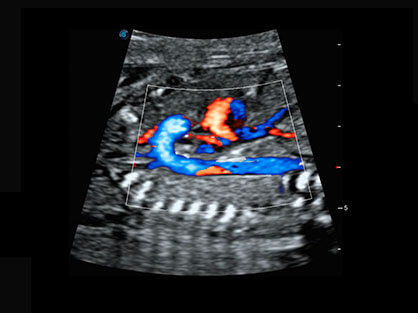

可同时显示组织结构表面和内部的轮廓信息,达到透视效果,为临床提供更丰富的诊断信息。

自动获取标准切面,自动完成测量,帮助医生快速完成检查,同时提升测量准确性。